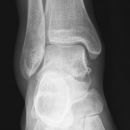

Talus Fraktur

Snowboard fracture Talus